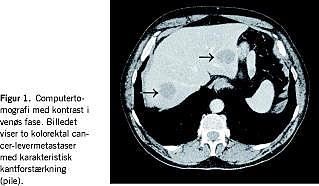

Ud fra computertomografi (CT) blev patienter med mak-simalt fire tumorer med en maksimumdiameter på 4 cm inkluderet i materialet. Mindst en læsion pr. patient var biopsiverificeret. I øvrigt hvilede diagnosen på CT med intravenøs kontrast - dvs. påvisning af hypovaskulære læsioner med karakteristisk kantforstærkning (Figur 1 ). Patienter med kendt ekstrahepatisk tumorspredning, uregulerbar koagulopati eller tumorer beliggende mindre end 1 cm fra galdeblæren, de centrale galdeveje eller tarmen blev ekskluderet.